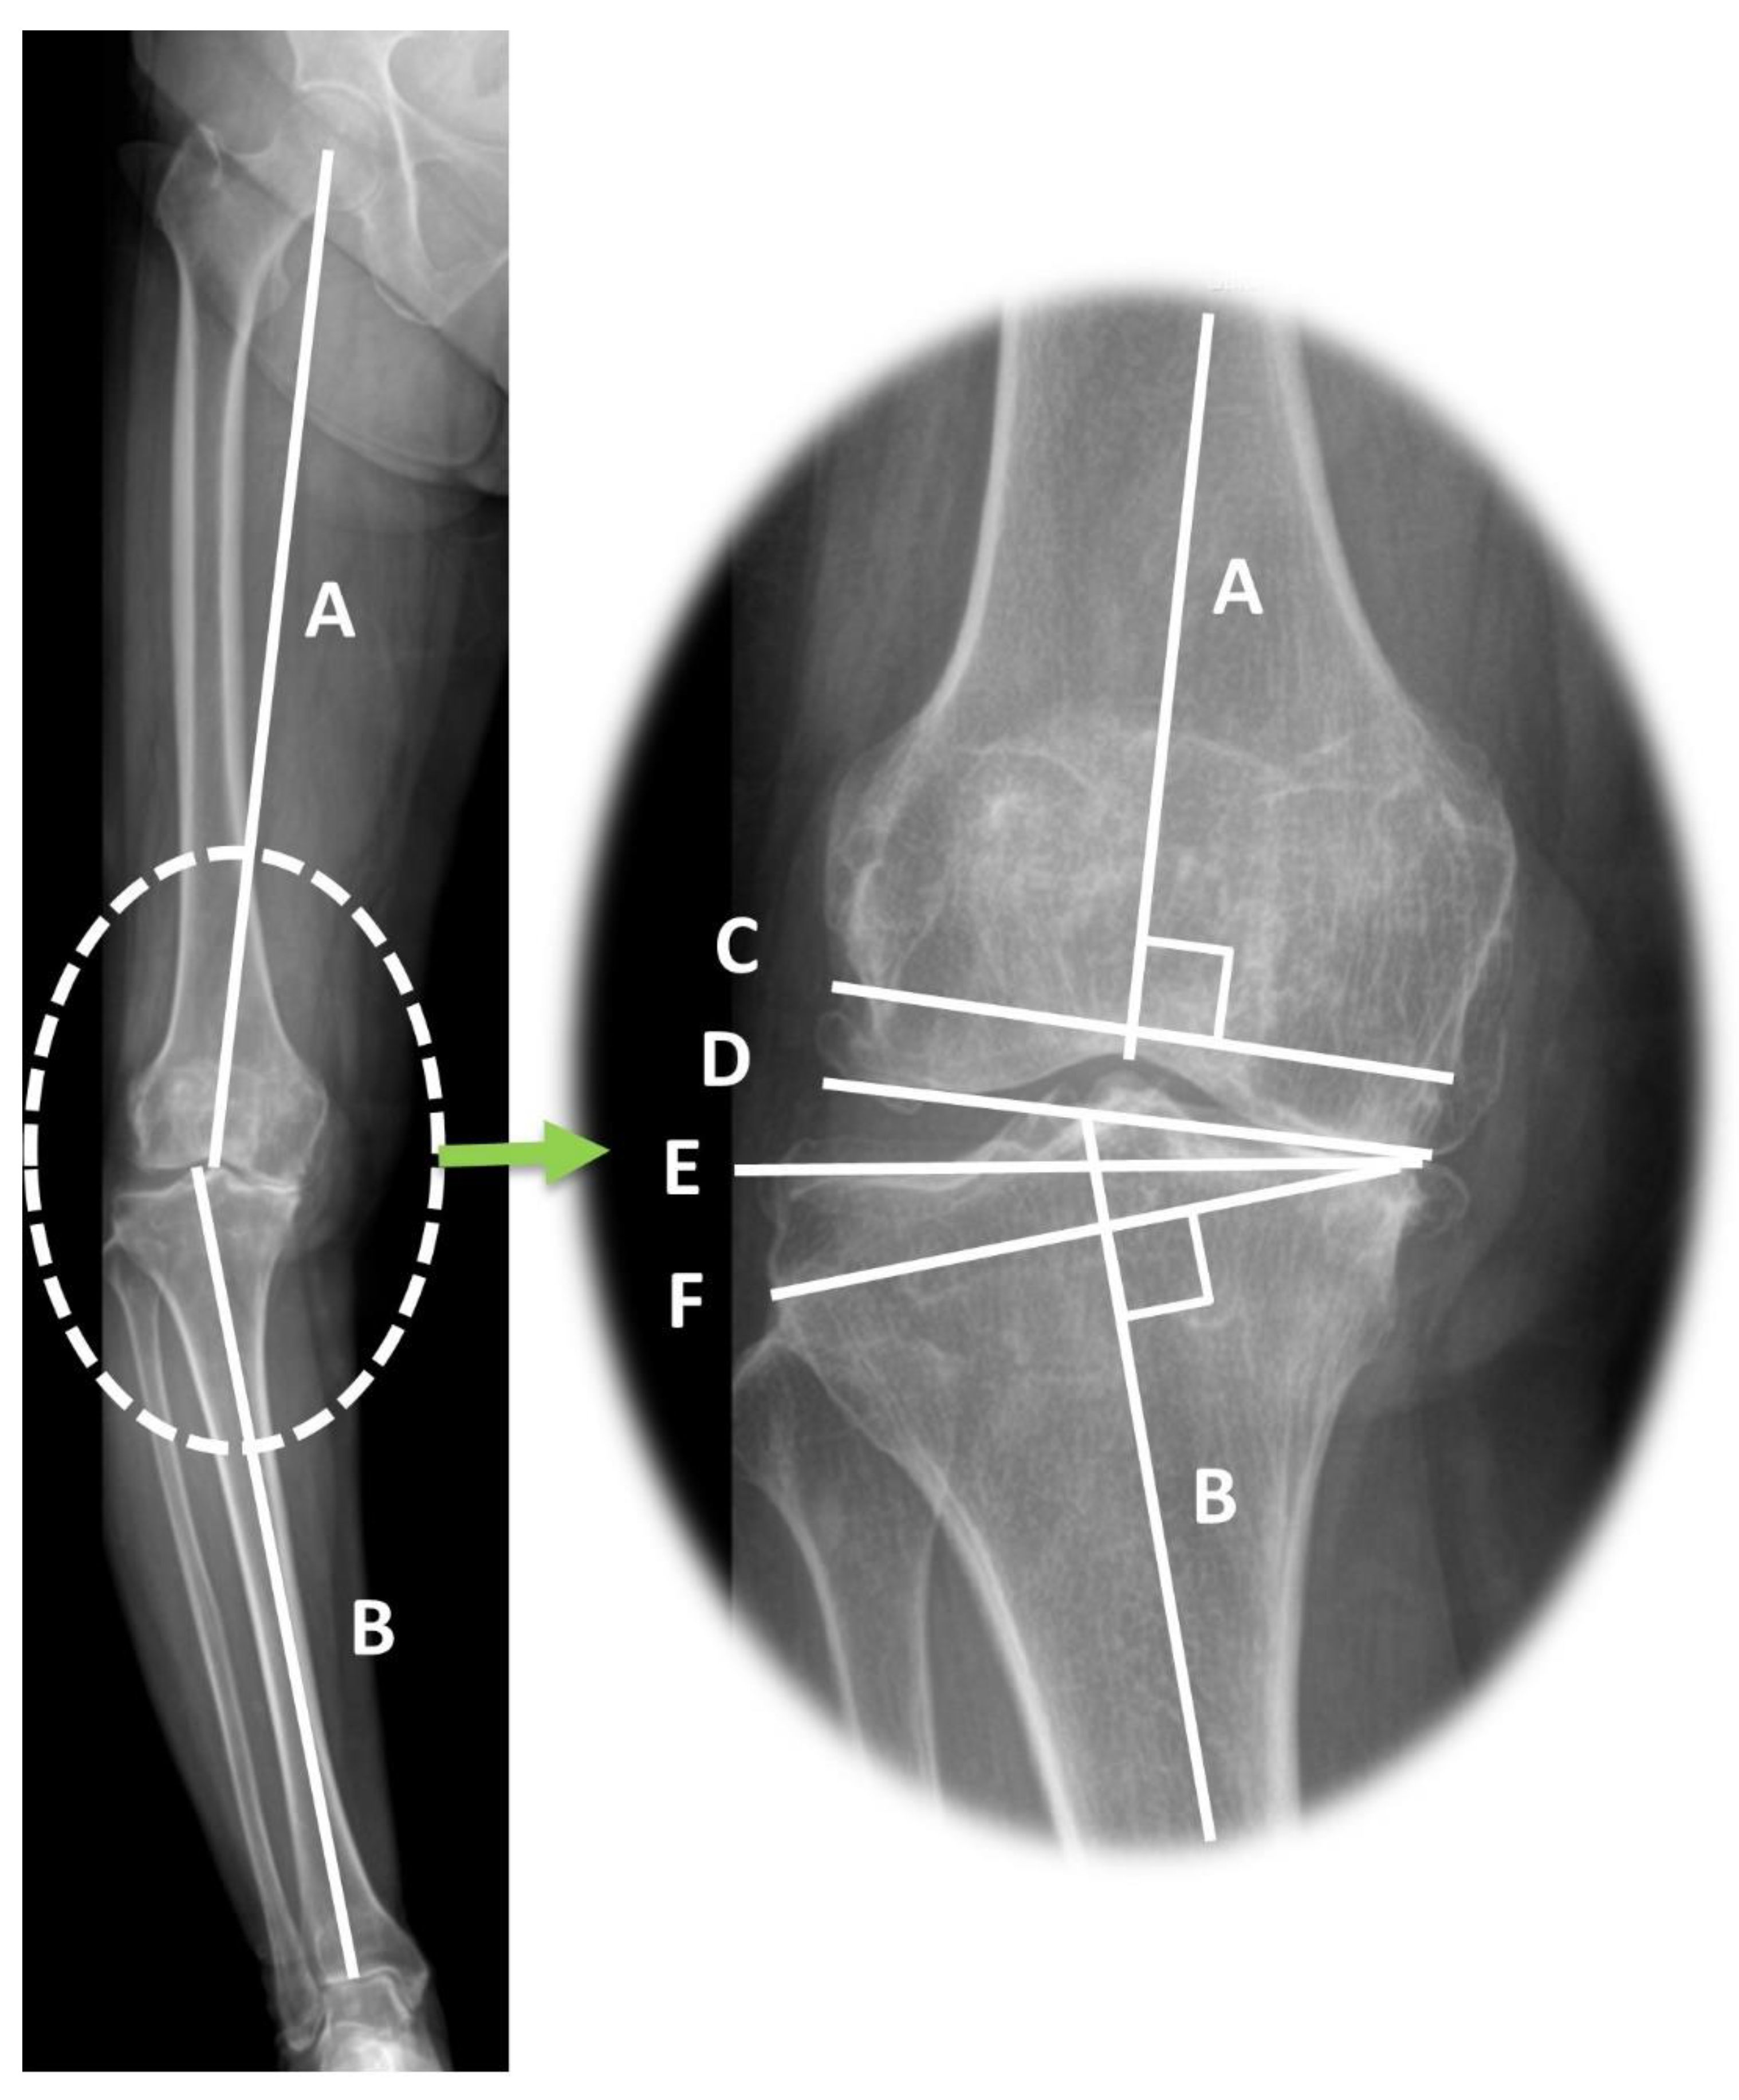

Preoperative radiographic parameters representing coronal alignment of the lower extremity were measured using a measurement tool in the picture archiving system software (Centricity Enterprise Web; 2006 GE healthcare, Chicago, IL, USA). The HKA varus angle was defined as the acute angle between the mechanical axes of the femur and tibia, which are the lines connecting the centers of the hip, knee, and ankle [21,22]. The mechanical lateral distal femoral angle (mLDFA) was measured as the lateral angle between the mechanical axis of the femur and the distal femoral joint line. The medial proximal tibial angle (MPTA) was defined as the medial angle between the mechanical axis of the tibia and the tangent to the tibial plateau line [9] (Figure 3). The joint line convergence angle (JLCA) and JLCA under varus/valgus stress were measured on standing anteroposterior and stress radiographs (Figure 4). JLCA was defined as the angle between the line connecting the articular surfaces of the distal femur and the proximal tibia [19]. The medial JLCA apex (varus) was assessed as positive, while the lateral JLCA apex (valgus) was measured as negative [23]. JLCA was also measured on the stress radiograph, which was taken under varus or valgus stress of 150 N to the knee in extension using a Telos device (Fa Telos, Medizinisch-Technische, Greisheim, Germany). All radiographic values were measured twice by two orthopedic surgeons with an interval of 2 weeks between measurements.

Figure 3.

Limb coronal alignments and bone cutting lines demonstrated in standing long leg radiograph. A: Mechanical axis of the femur, B: Mechanical axis of the tibia, C: Distal femur cutting line, D: Distal femoral articular surface, E: Proximal tibial articular surface, F: Proximal tibial cutting line. HKA varus angle: acute angle between A and B; mLDFA: lateral angle between A and D; MPTA: medial angle between B and E; JLCA: angle between D and E. The distal femur (line C) and proximal tibia cutting (line F) were perpendicular to the mechanical axis of the femur (line A) and the mechanical axis of the tibia (line B). The gap between lines C and F (extension gap) shows a trapezoidal gap after bone cutting.

The primary cause of mediolateral gap differences (trapezoidal gap) in severe varus knees is the principle of mechanically aligned bone cutting. In mechanically aligned TKA, the distal femur and proximal tibia are resected at a right angle (90°) to their respective mechanical axes [34,35]. The angle between the mechanical axis and bone cutting line and the thickness of the distal femur and proximal tibia bone cutting is shown in Figure 3. Lines C and F indicate bone-cutting lines that are perpendicular to their respective mechanical axes (lines A and B). The severity of the varus deformity of the proximal tibia and distal femur is directly proportional to the angle between tangential lines of the distal femur and proximal tibia articular surface and osteotomy line (∠C,D and ∠E,F, Figure 3). As a result of mechanically aligned bone cutting on varus-deformed knees, a larger thickness of bone is inevitably cut in the lateral compartment [36,37]. The discrepancy in bone resection between the medial and lateral sides is more prominent in the proximal tibia than in the distal femur. Every osteoarthritic knee with varus alignment shows proximal tibia varus, but distal femur varus is not always observed [23]. In addition, in the present study, the proximal tibia showed a greater varus magnitude than the distal femur (mean MPTA 84.3° and mLDFA 89.5°). For this reason, trapezoidal flexion and extension gaps are more likely to originate from proximal tibia varus deformity than from distal femur varus deformity. This finding also supports the result of the present study that MPTA was correlated with FGD and EGD and was an influencing factor for EGD.